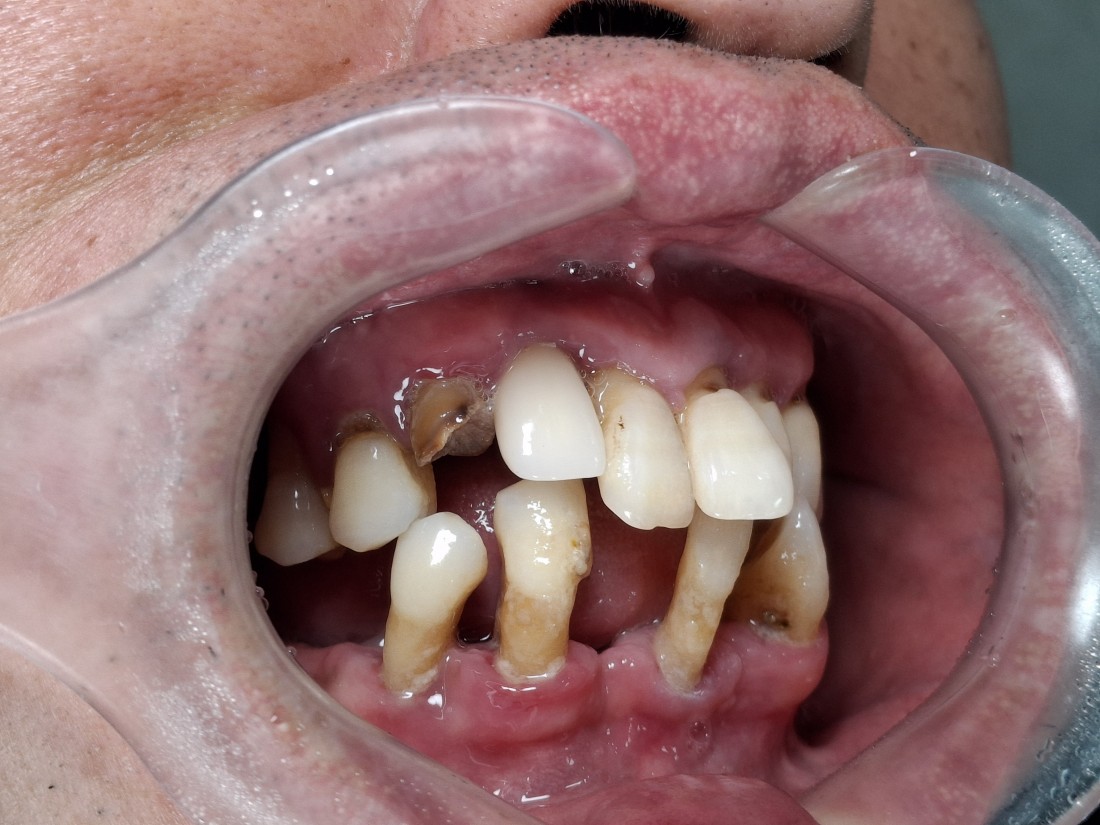

광주 전체임플란트

치료 케이스가 많은 치과가

잘하는 치과입니다.

광주 전체임플란트 케이스만

수 백가지로 정리하여

위의 홈페이지에 올려드리고 있는데요.

치과의사도 경험이 풍부한 사람이

여러 케이스를 다 다뤄보았기 때문에

좋은 임플란트 실력을 믿을 수 있습니다.

광주 전체임플란트를 생각할 때

임플란트 하나당 가격만 생각하시나요?

저렴한 개당 가격이 중요한 것이 아니고,

최소한의 개수를 식립하여 최대의 효과를 낼 수 있다면

전체 견적이 훨씬 줄어드는 효과가 있습니다.